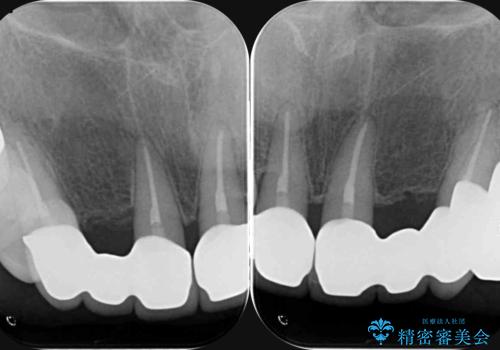

- 20年前に入れたブリッジの見た目の改善を求めて来院されました。

丁寧に現在装着されているブリッジを除去後、精度の高いジルコニアブリッジで審美性の改善を計画します。

前歯に限らず拡大鏡を用いた精密な形成・シリコンを用いた精度の高い印象を徹底することで治療全体の質を高め、審美性だけでなく長期的な予後を期待することができます。